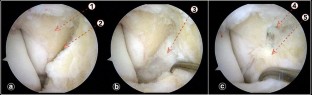

During diagnostic arthroscopy, 12 patients showed an isolated anterior talofibular ligament (ATFL) injury, and in one patient, both the ATFL and calcaneofibular ligament were affected. Arthroscopic examination of the deltoid ligament demonstrated a tear affecting the anterior area of the ligament in all cases. The tear was described as an "open book" tear, because the ligament was separated from the medial malleolus when applying passive internal rotation of the tibio-talar joint. This gap was closed when the tibio-talar joint was in neutral rotation or externally rotated. All patients reported subjective improvement in their ankle instability after the arthroscopic all-inside ligaments repair. The median AOFAS score increased from 70 (44–77) preoperatively to 100 (77–100) at final follow-up.

Fig. 1